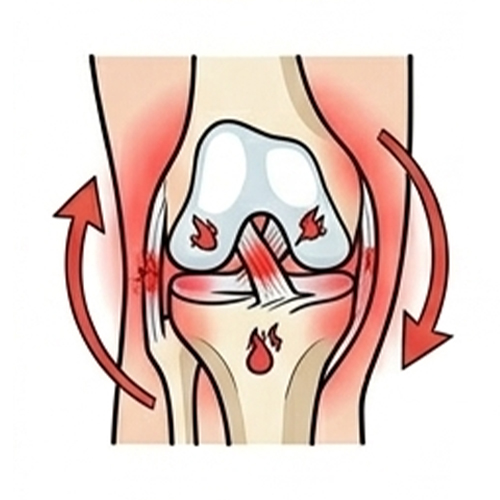

Ligament Injury (ACL, MCL, LCL

Pain, swelling, and instability following sports or twisting injuries.

Meniscus Tear

Deep joint pain, locking, or clicking after a twist or squat.